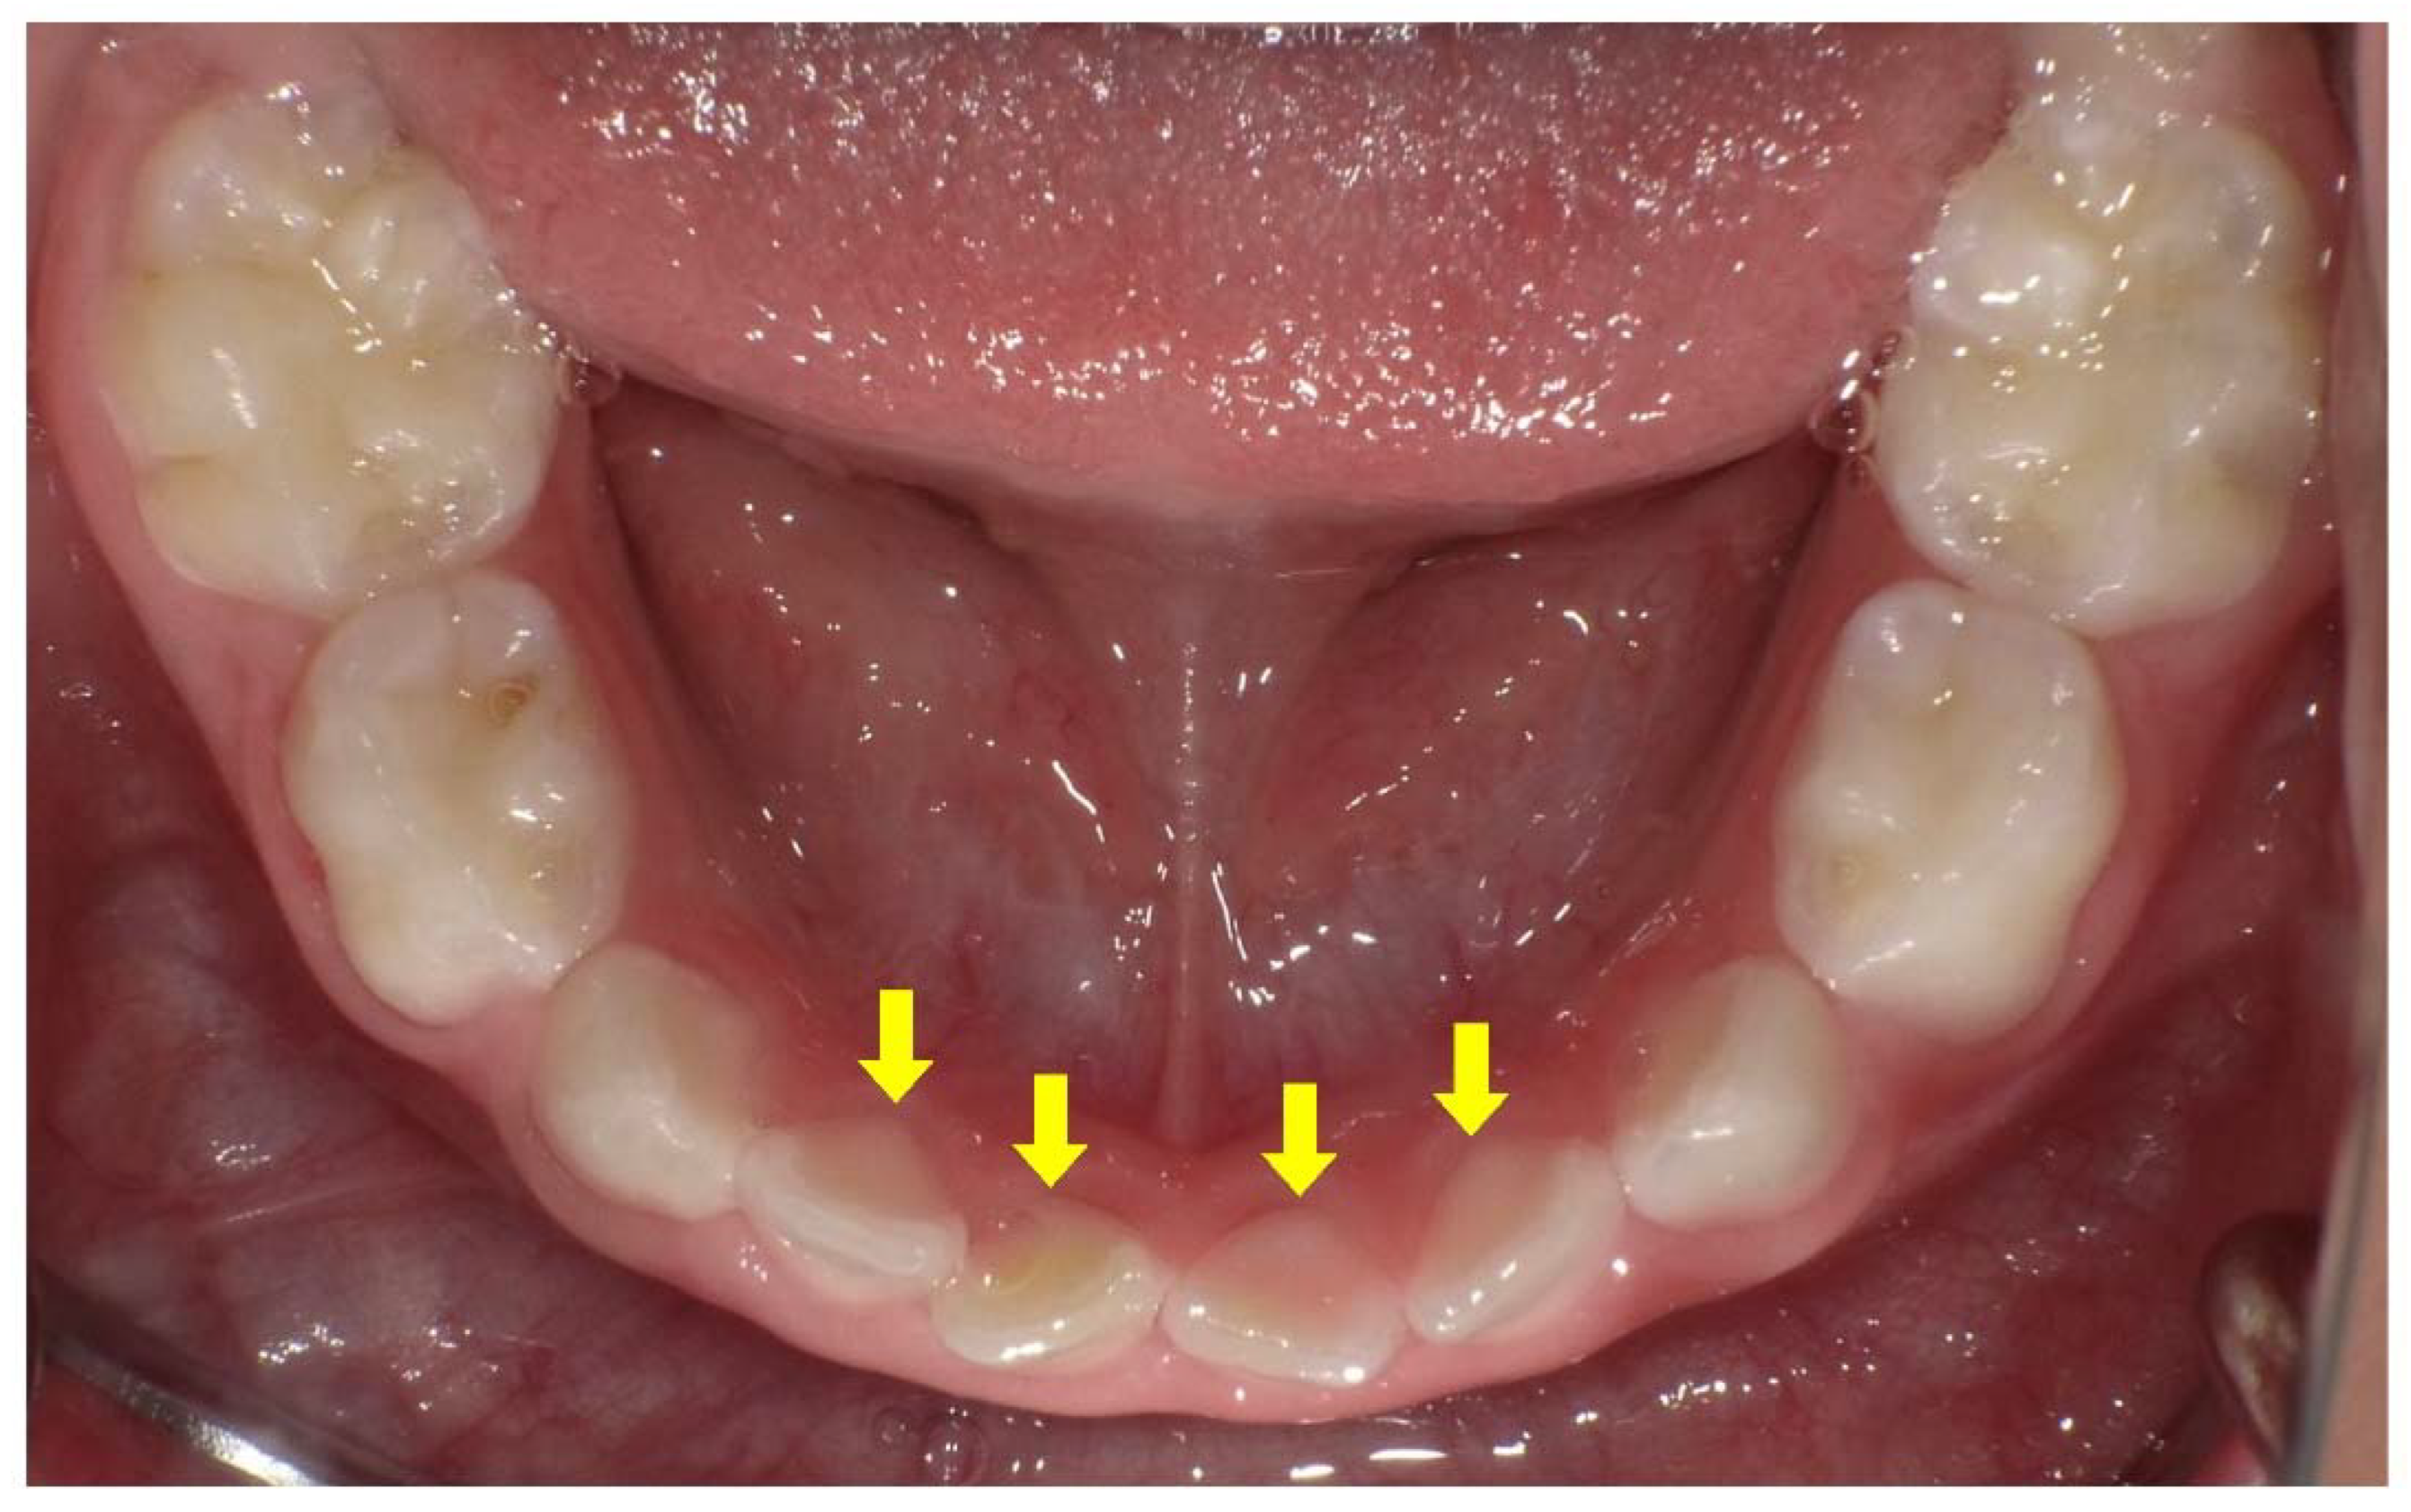

- Wato, K.; Okawa, R.; Matayoshi, S.; Ogaya, Y.; Nomura, R.; Nakano, K. X-linked hypophosphatemia diagnosed after identification of dental symptoms. Ped. Dent. J. 2020, 30, 115–119. [Google Scholar] [CrossRef]

- Douyere, D.; Joseph, C.; Gaucher, C.; Chaussain, C.; Courson, F. Familial hypophosphatemic vitamin D-resistant rickets—Prevention of spontaneous dental abscesses on primary teeth: A case report. Oral Surg. Oral Med. Oral Pathol. Oral Radiol. Endod. 2009, 107, 525–530. [Google Scholar] [CrossRef] [PubMed]

- Lee, B.N.; Jung, H.Y.; Chang, H.S.; Hwang, Y.C.; Hwang, I.N.; Oh, W.M. Dental management of patients with X-linked hypophosphatemia. Restor. Dent. Endod. 2017, 42, 146–151. [Google Scholar] [CrossRef] [PubMed]

- Akif, D.; Tuba, A.A.; Esra, E.; Tulga, Ö.F. Dental Management of Hypophosphatemic Vitamin D Resistant Rickets. J. Pediatr. Res. 2018, 5, 221–224. [Google Scholar]